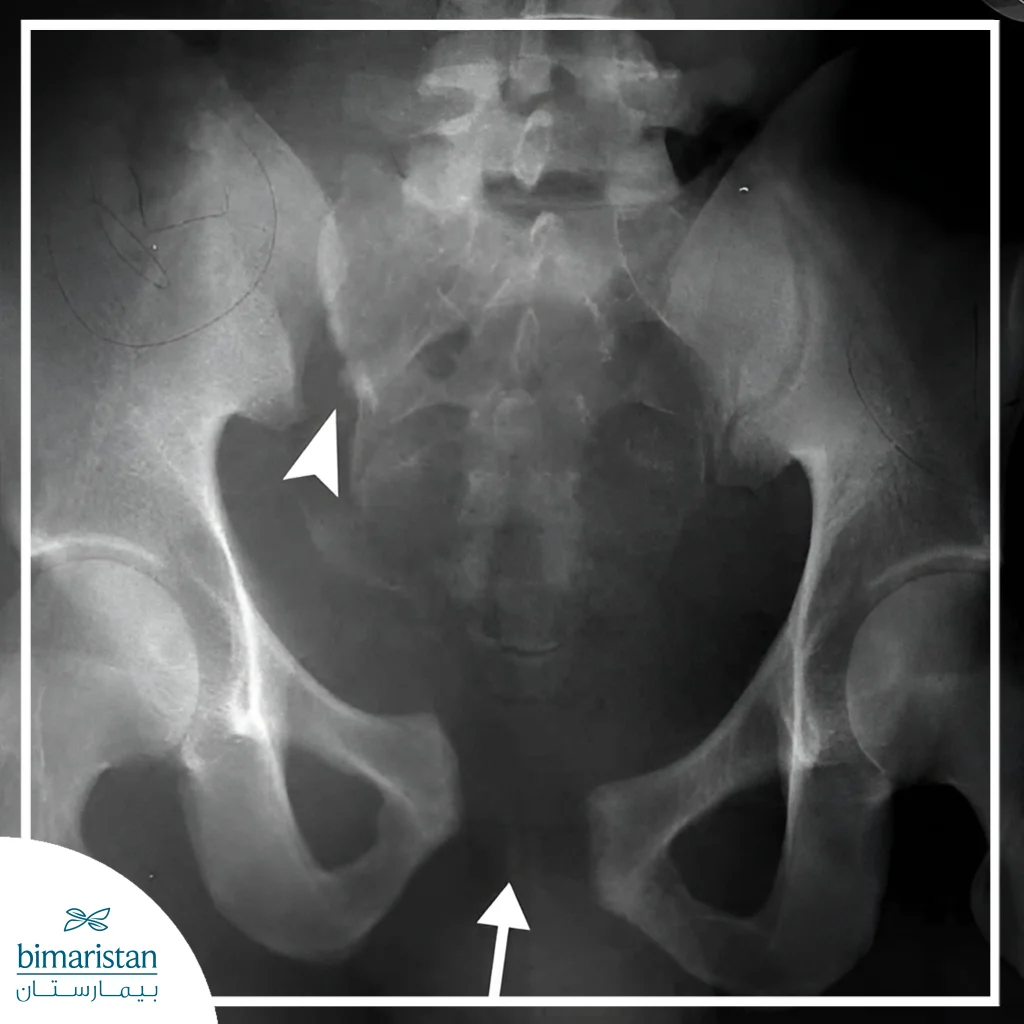

الأشعة السينية

الأشعة السينية هي أولى تقنيات التصوير المستخدمة لتأكيد وجود الكسر وتحديد نمطه، مثل الكسور المغلقة أو المفتوحة والكسر الجزئي أو الكامل، وعلى الرغم من فعاليتها، قد لا تكشف دائماً عن الكسور البسيطة أو كسور الإجهاد، لكنها توفر معلومات أساسية لتخطيط علاج كسر الحوض.